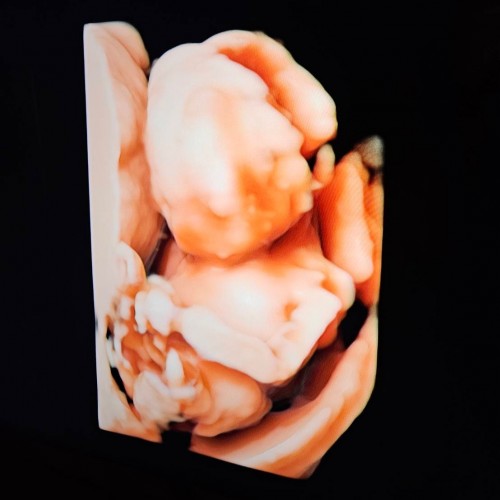

น้อง 18 วีคค่ะ ☺️ ยังเอเลี่ยนอยู่555